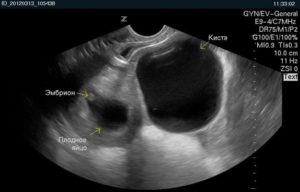

Диагностировать патологию можно при помощи УЗИ, осмотра гинеколога, лапароскопии. Встречается такая киста и в зрелом, и в юном возрасте.

Если киста яичника при беременности не проявляется клинически и имеет небольшие размеры, то лечение не обязательно. Тактика докторов в этом случае будет выжидательной. Чтобы контролировать развитие образования рекомендуется периодический осмотр у гинеколога и ультразвуковая диагностика.

Киста может регрессировать и самостоятельно исчезнуть (обычно это происходит к 20 неделе беременности), поэтому зачастую никакого лечения не требуется, а только динамическое наблюдение у врача и УЗИ. Даже если после 20 недели киста не исчезла, то велика вероятность, что это случится после рождения ребенка.

Тем не менее, контролировать эту патологию при помощи УЗИ-диагностики и осмотра гинеколога необходимо обязательно.